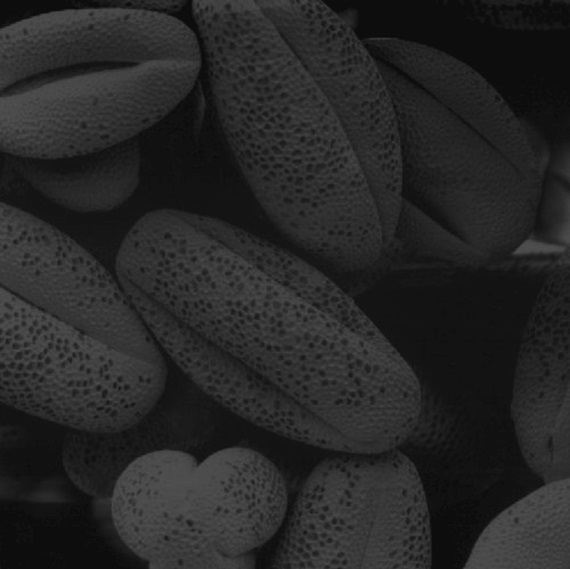

* Image processing algorithms added * Example images included * Issues resolved * class added * Naming issues fixes * Create file_path

59 KiB

570x569px